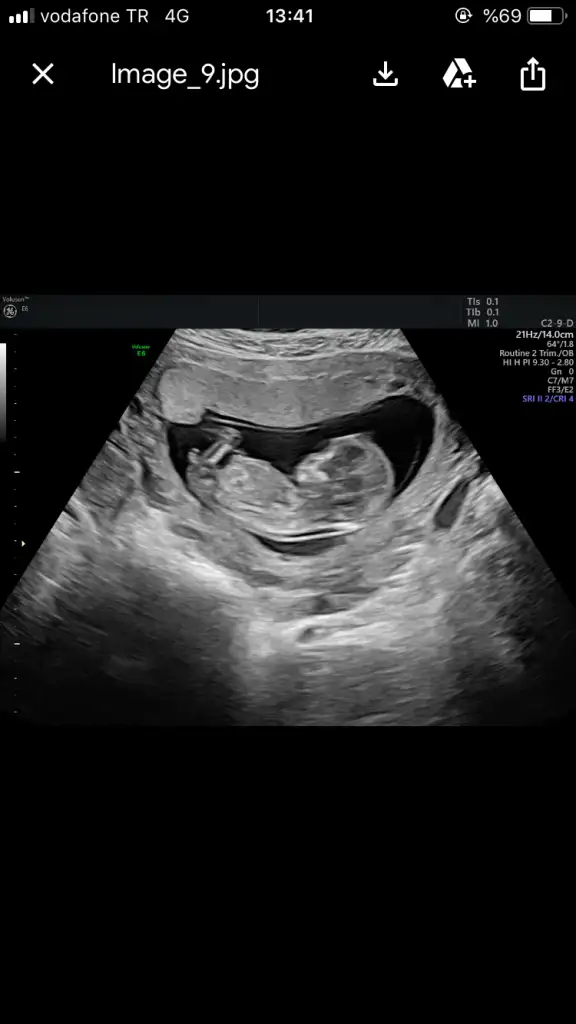

Nub icin Çok minik kese icin büyük nub icin 11 12 13 haftalar olmalı kese için 6-7 olmaliBugün yani 8+4 karından usg, kese uzun erkek mi oluyordu ben pek anlamıyorum baya uzun kese bir oğlan daha mı geliyor acaba

Buna göre erkek gibi ama en iyi 11 12 13 haftalar olmalıKarından bakıldı 7+1

Buna göre erkek tabiki en iyi 11 12 13 haftalar olmalıEki Görüntüle 2685703

Daha önce 7+4 ken gondermisiz kiz gibi denilmis.Buna herkes erkek demis.Senin gibi.Buna göre erkek tabiki en iyi 11 12 13 haftalar olmalı

Evet 6. 7. hafta dan sonra değişirDaha önce 7+4 ken gondermisiz kiz gibi denilmis.Buna herkes erkek demis.Senin gibi.